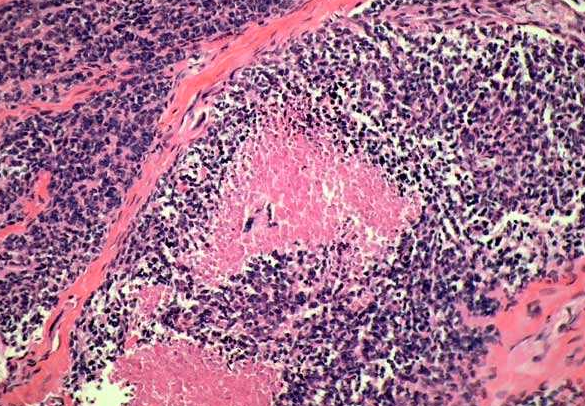

Ewing’s sarcoma and primitive neuroectodermal tumor (PNET) refer to an aggressive malignant tumor involving bones and extraskeletal sites and show a characteristic t(11;22)(q24;q12) and distinct immunophenotype in most cases. The tumors usually seen between ages 5-15 years involve shafts of long bones and arise from within medullary cavity. Most cases show necrosis, at least focally (pink necrotic cells in the center), and a high mitotic rate. The solid tumor clusters are separated by fibrous bands.

[EWING’S SARCOMA/PNET, BONE] – The tumor cells are rather undifferentiated morphologically and are arranged in large sheets and clusters separated by thick fibrous bands. Necrosis may be focal or extensive (arrowhead) and may render diagnosis difficult in small biopsy specimens with few viable cells. FISH study for typical t(11;22) may prove diagnostic in smaller samples.

Ewing’s sarcoma/PNET is one of several so-called “Small blue round cell tumors.” Included among these tumors are lymphoma (especially lymphoblastic lymphoma), small cell neuroendocrine carcinomas (lung and other sites), desmoplastic small round cell tumor (abdominal and extra-abdominal), embryonal rhabdomyosarcoma, small cell variant of melanoma, and many other tumors with similar morphology. A correct diagnosis would require correlation of clinical, radiographic, morphologic, immunohistochemical, and molecular findings.

[EWING’S SARCOMA/PNET, BONE] – One of the characteristic features of ES/PNET is the presence of cytoplasmic PAS positive glycogen granules (arrowhead) which dissolves upon treatment with diastase (PAS-D). However, PAS positive cytoplasmic glycogen can be found in some cases of precursor T-cell lymphoblastic lymphoma making the differentiation difficult. In contrast to cases of ES/PNET the cytoplasmic PAS-positive granules are fewer and smaller in lymphoblastic lymphoma. However, the presence of PAS-positive cytoplasmic glycogen helps exclude small cell neuroendocrine carcinomas.

[EWING’S SARCOMA/PNET, BONE] – The neoplastic cells are small to intermediate in size with scant cytoplasm, indistinct cell membranes, round to slightly angulated nuclei containing indistinct to small nucleoli. The cells may be so undifferentiated that a morphologic distinction from any of the other small blue round cell tumors may be impossible on morphology alone. However, pseudo- rosette or true rosette formation may be present suggesting a neuroectodermal differentiation. In some tumor, however, mild pleomorphism is present with divergent immunohistochemical differentiation.

Ewing Sarcoma CD99 positive